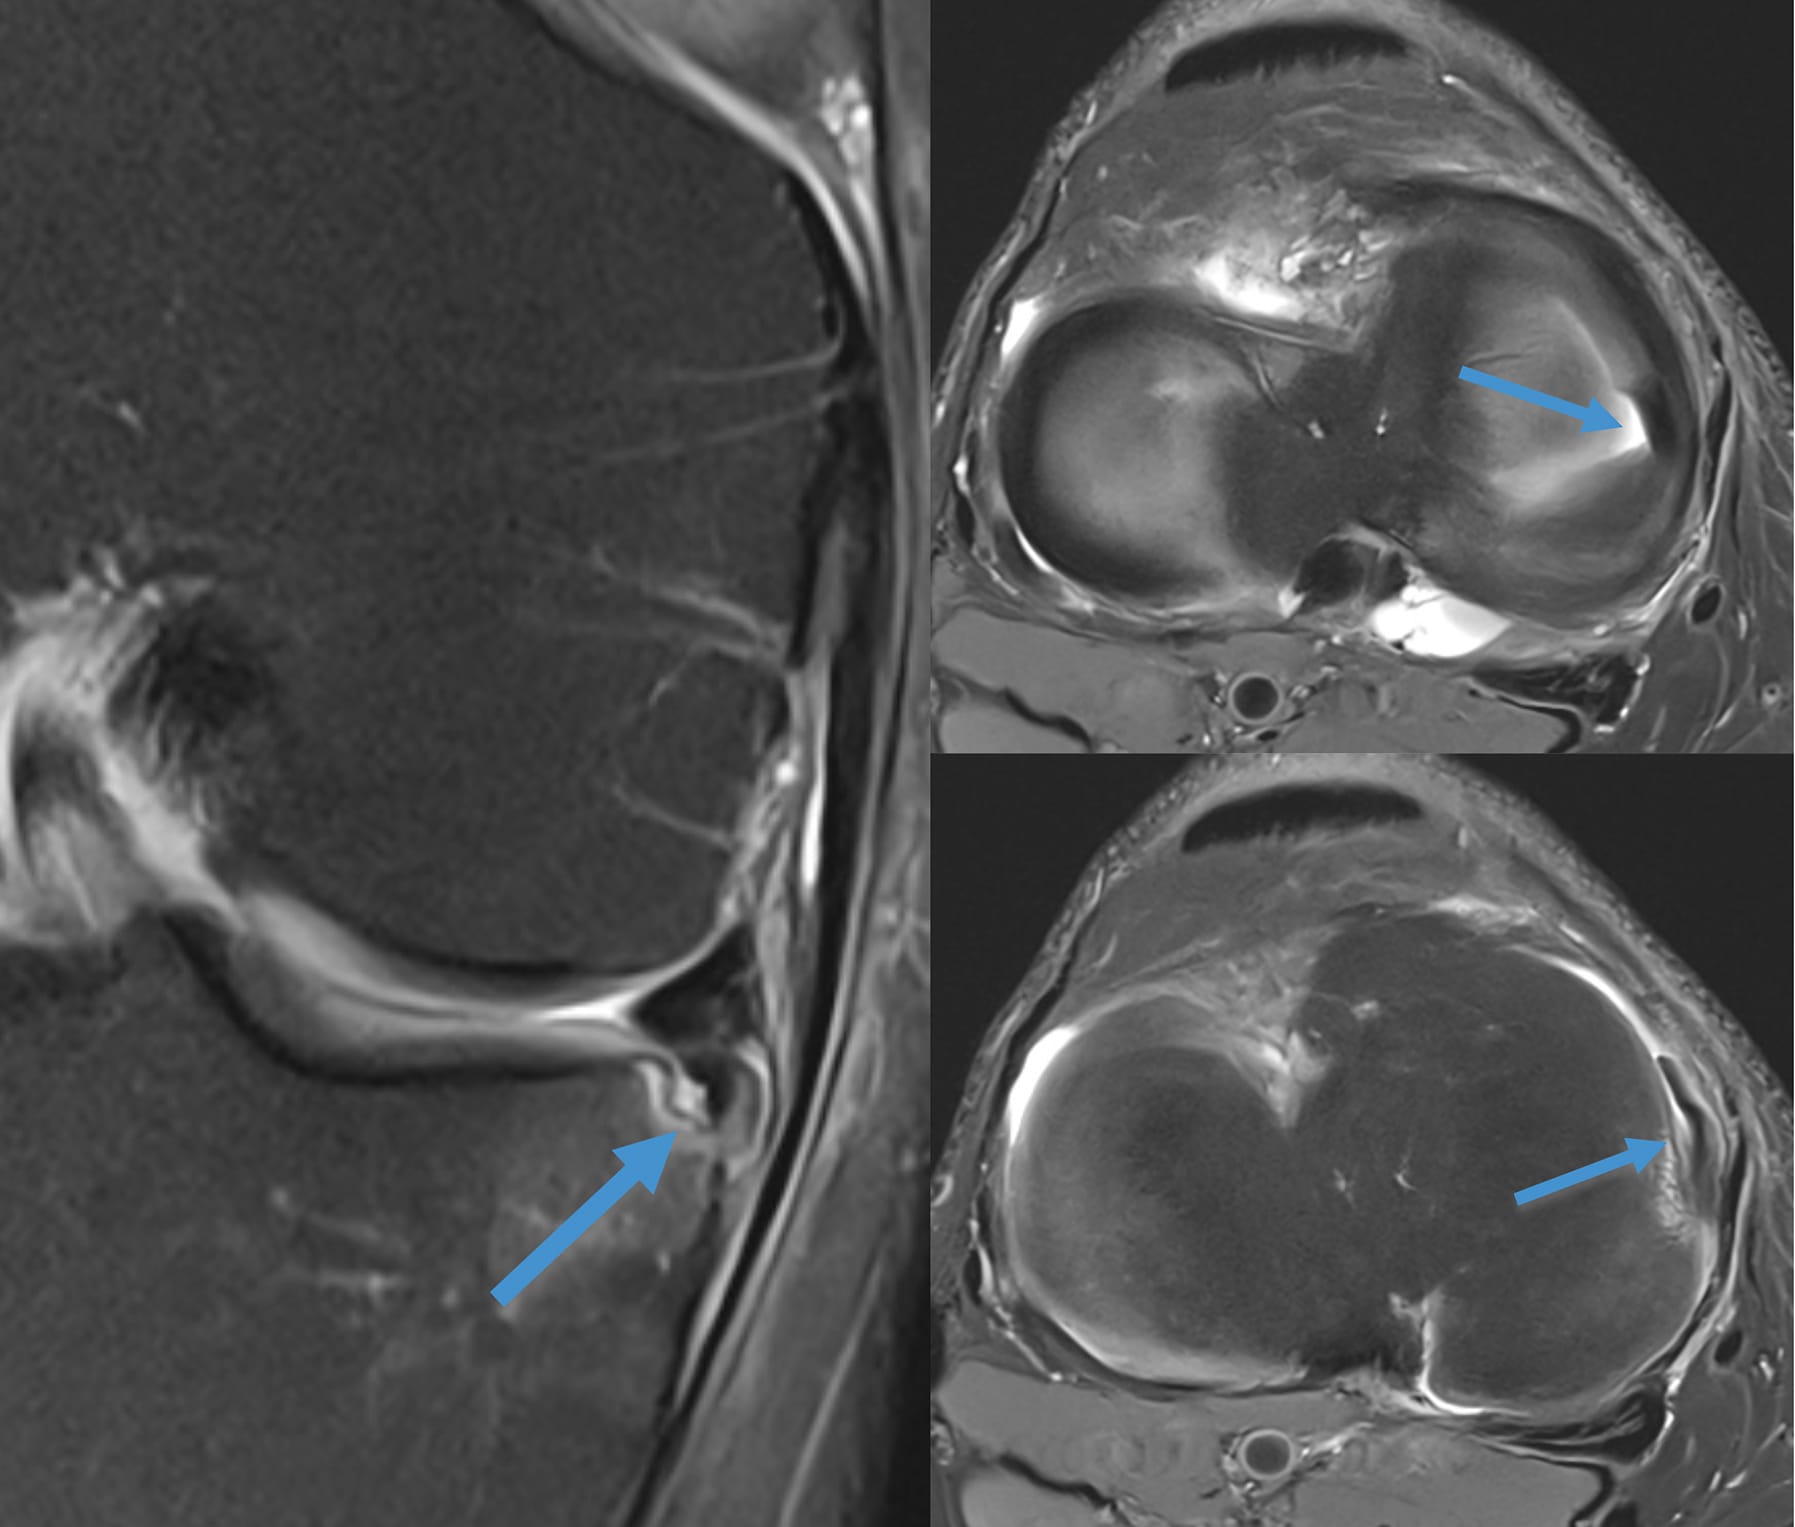

Fissure méniscale avec fragment méniscal déplacé

Figure 1 - Amputation du bord libre de la corne postérieure du ménisque interne en rapport avec le déplacement d’une languette méniscale vers le récessus méniscal inférieur. À ce niveau le plateau tibial est le siège d’une impaction mécanique localisée